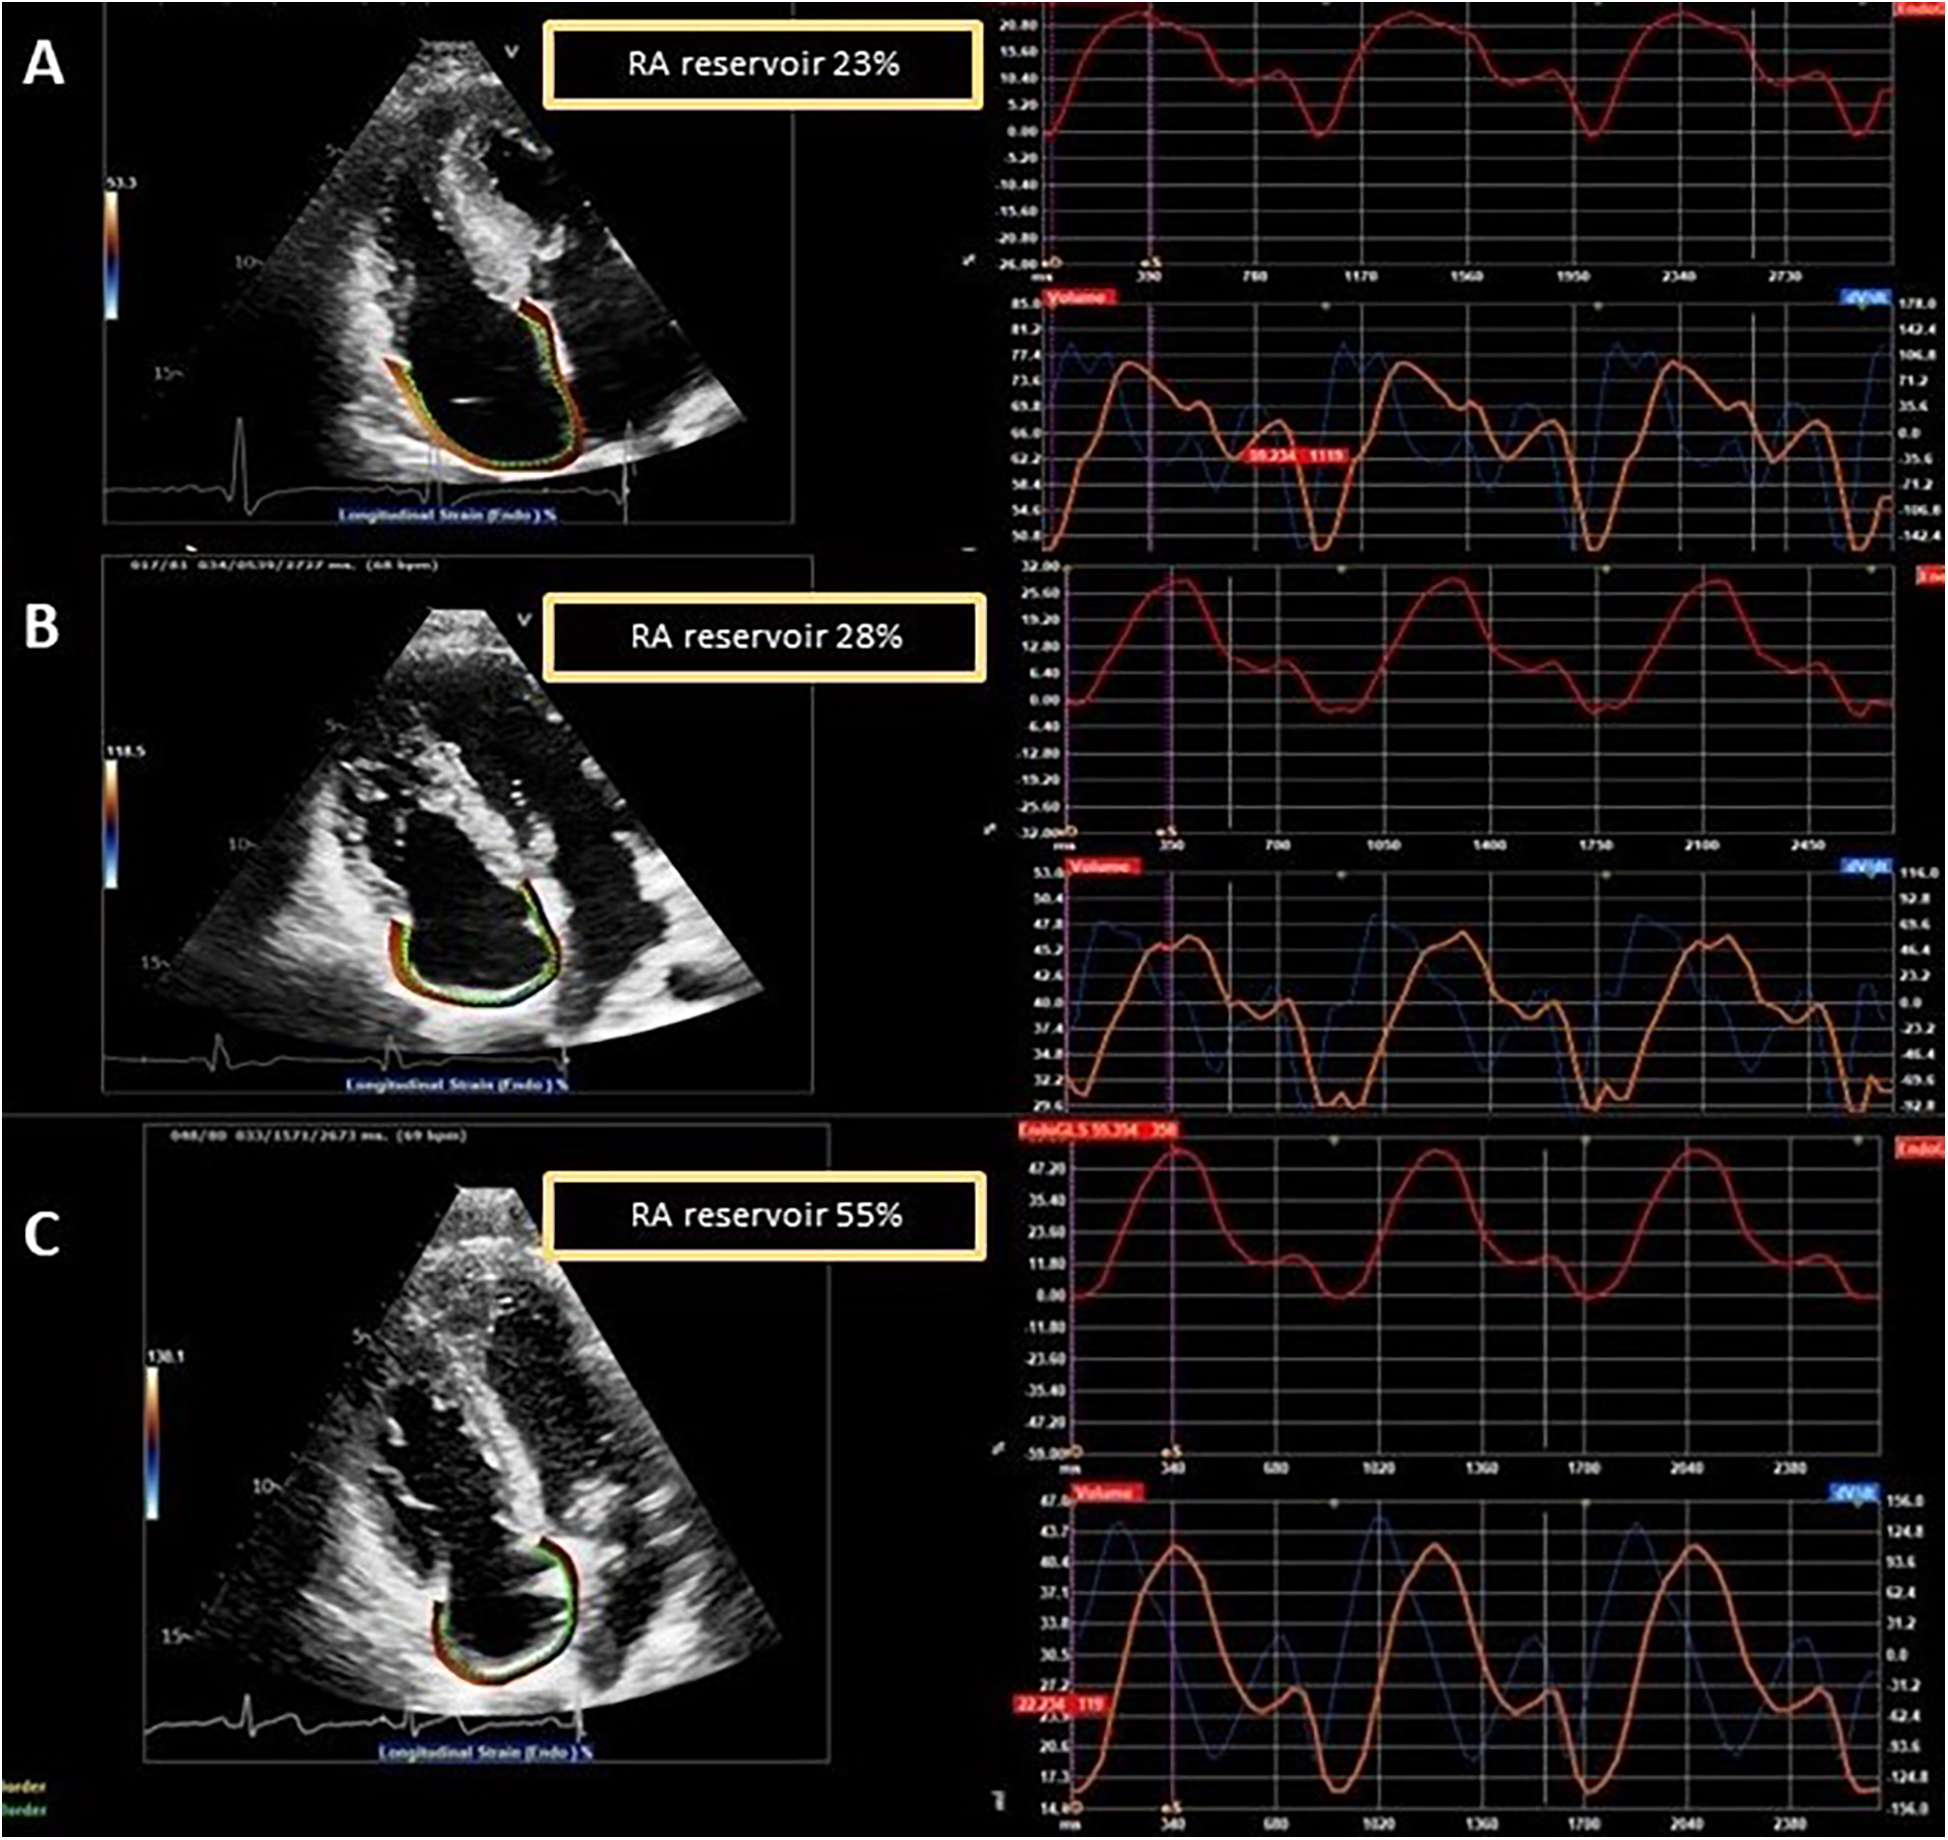

Among the LVH+ group of patients, the median maximal wall thickness was 16 mm (IQR: 15–20) and, as expected, several differences emerged between the three groups (LVH+ vs. LVH− vs. controls), as shown. Of interest, the LVH− patients differed from controls for lower values of LV-GLS (p = 0.025), lateral e′ (p = 0.010), septal and lateral a′ (p < 0.001), RA reservoir (31.3 ± 9.6 vs. 41.9 ± 8.3%, p < 0.001), and contractile (8.8 ± 4.4 vs. 18.0 ± 4.9%, p < 0.001) strains. Figure 2 shows an example of RA strain assessment in a patient with FD LVH+, in a patient with LVH−, and in an HC.

Figure 2

Examples of RA strain assessment in a patient with FD and left ventricular hypertrophy (LVH+, A), in a patient with FD without left ventricular hypertrophy (LVH−, B), and in a healthy control (C).